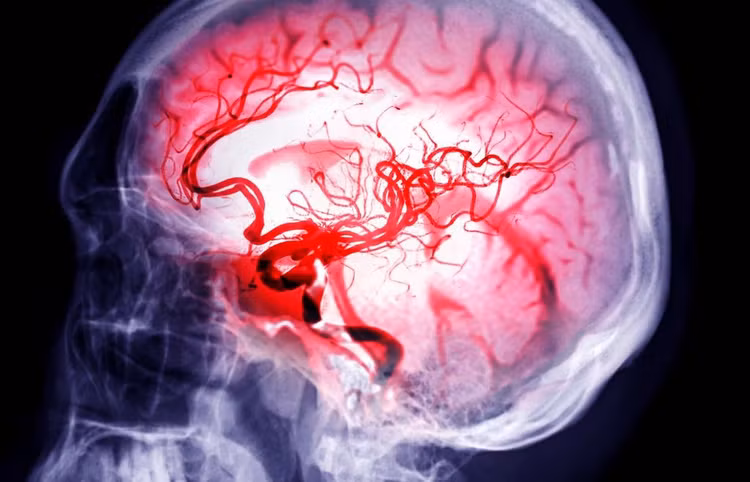

| Ông Hameroff giải thích cách các nhà nghiên cứu đặt các cảm biến nhỏ trên não của 7 bệnh nhân mắc bệnh mãn tính vài phút trước khi họ ngừng hỗ trợ sự sống, cho phép họ ghi lại hoạt động sau khi huyết áp và nhịp tim của mỗi bệnh nhân giảm xuống mức 0. Ảnh: The Project Unity. |

| Tiến sĩ Hameroff chia sẻ với người dẫn chương trình Jay Anderson trong chương trình YouTube Project Unity rằng, các nhà khoa học quan sát thấy “mọi thứ dường như biến mất nhưng sau đó lại có sự bùng nổ của hoạt động trong não. Đó có thể là trải nghiệm cận tử hoặc linh hồn rời khỏi cơ thể”. Ảnh: TheProjectUnity/X. |

| Đồng thời, Tiến sĩ Hameroff cho hay điều này có thể giải thích tại sao con người vẫn có nhận thức trong trạng thái não bộ có năng lượng thấp như gây mê, ngủ sâu hoặc thậm chí là trải nghiệm cận tử. Ảnh: TheProjectUnity/X. |

| Các nhà nghiên cứu cho biết lời giải thích khả thi nhất là các xung điện được giải phóng khi não bị thiếu oxy. Ảnh: samunella – stock.adobe.com. |

| Ông Hameroff nói: “Khi tim ngừng đập và máu không còn lưu thông, các vi ống trong não mất đi trạng thái lượng tử của chúng. Tuy nhiên, thông tin lượng tử trong các vi ống không bị phá hủy; nó không thể bị phá hủy và sẽ phân tán ra ngoài vũ trụ rộng lớn”. Ảnh: The University of Arizona. |

| Ông Hameroff giải thích thêm rằng, nếu bệnh nhân được hồi sức hoặc tỉnh lại, thông tin lượng tử này có thể quay lại các vi ống và khiến bệnh nhân trải nghiệm cảm giác đã có một trải nghiệm cận tử. Ảnh: Getty. |

| Tuy nhiên, nếu bệnh nhân không được hồi sinh và chết, thông tin lượng tử này có thể tồn tại bên ngoài cơ thể, có thể là vô thời hạn dưới dạng linh hồn. Ảnh: christianpublishinghouse. |